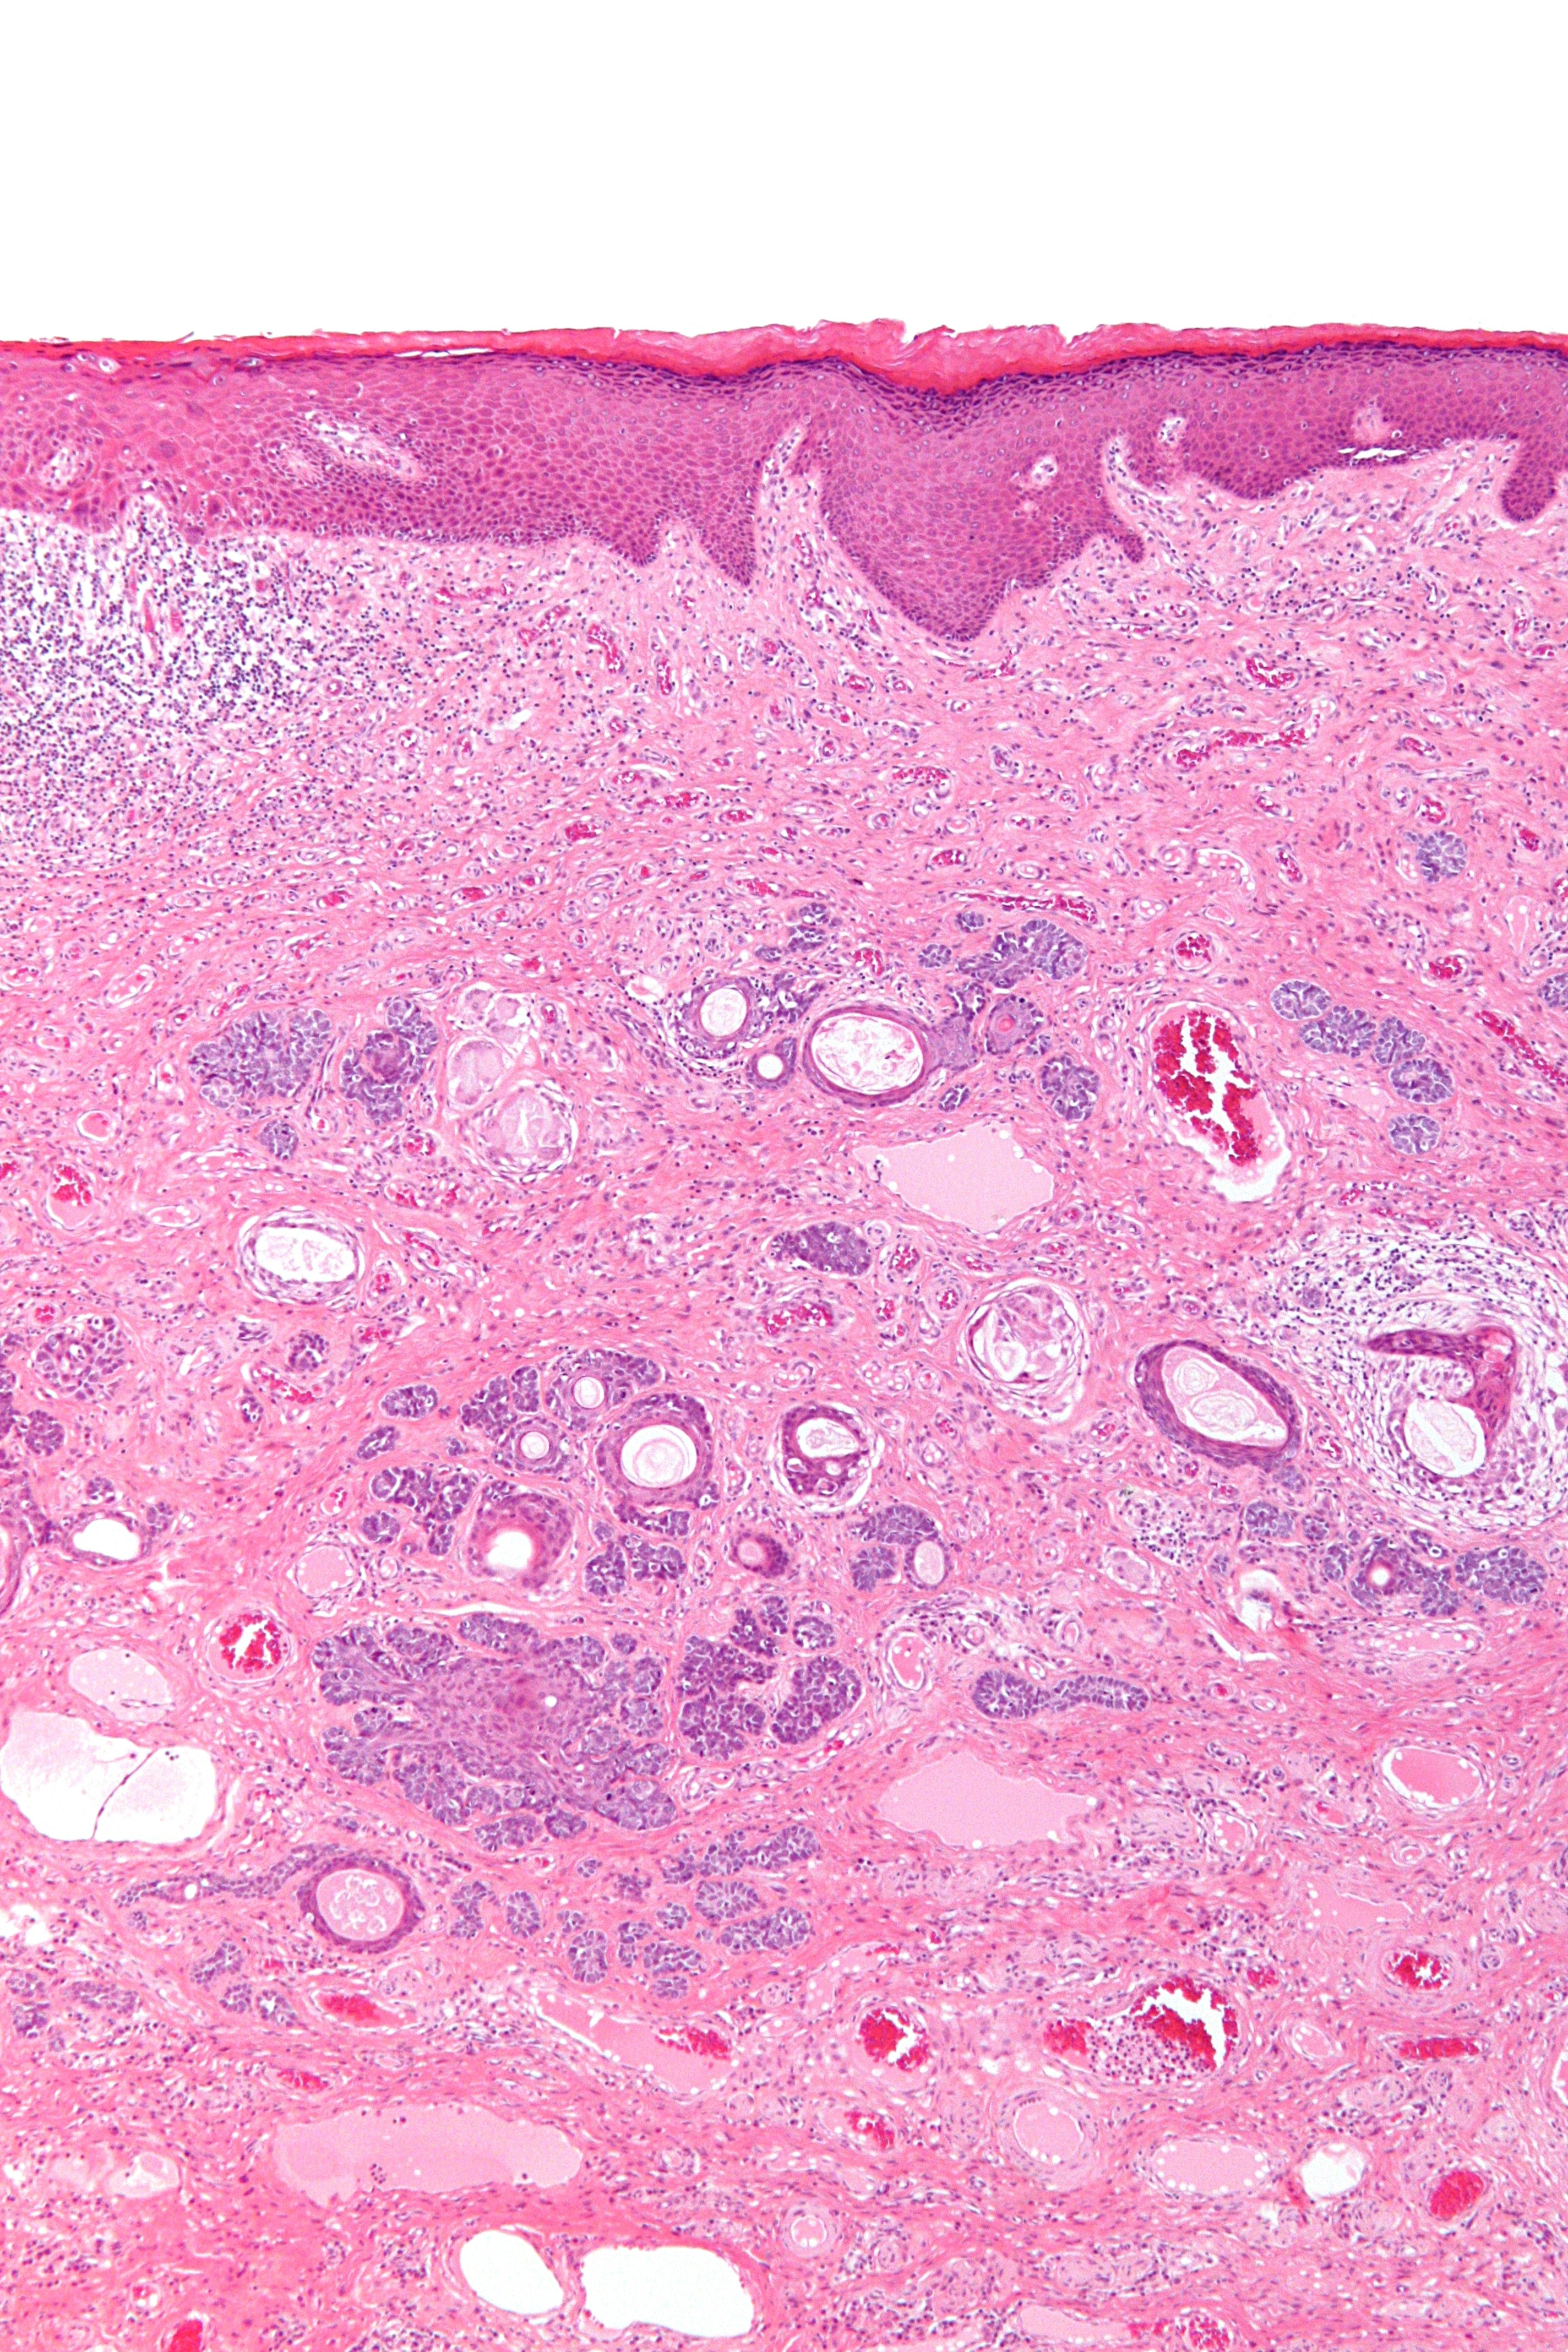

Histologie:Eilandjes van relatief monomorfe basaloïde cellen,

waarbij soms sprake is van perifere afzetting van de kernen. Deze ophoping van

cellen is in het bovenste deel van de dermis gelegen en vormt soms een continuïteit

met de epidermis. De eilandjes worden omgeven door een overmatige hoeveelheid

celrijk, fibreus stroma met buisformatie. Er kunnen tevens kleine hoorncysten,

omgeven door gelaagd plaveiselcelepitheel, uitgaande van de buitenste haarschachtcellen,

gezien worden. De hoorncysten kunnen ruptureren met een vreemdlichaam reuscelreactie

op vrij keratine tot gevolg. Foci van papillaire mesenchymale lichaampjes, oftewel

rudimentaire folliculaire papillen, zijn typisch.

| PA trichoepithelioom |

PA trichoepithelioom |